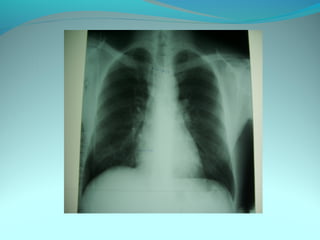

Cliché normal